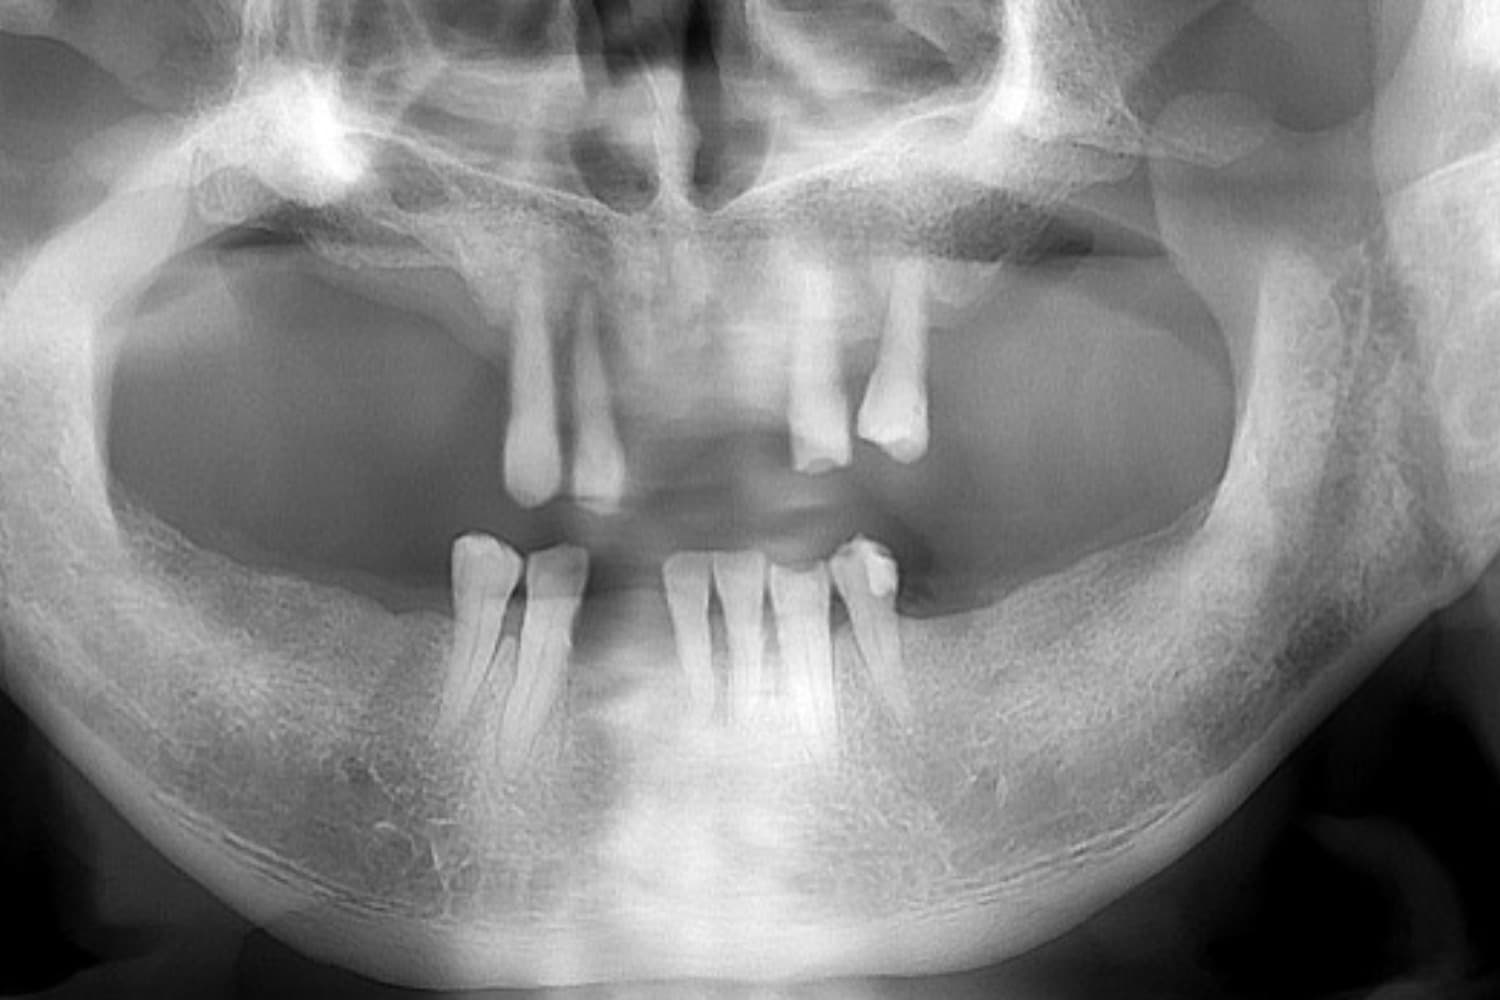

上下のインプラント治療

Before

上下の保存できない歯を抜歯して、インプラント治療で咬合機能の回復をおこなう

60代

女性

上下の入れ歯が合わない。しっかり噛めるようになりたい。